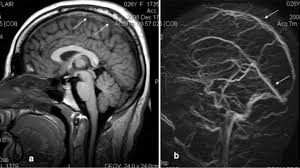

Cvst is a rare form of. Cerebral venous thrombosis (cvt) refers to occlusion of venous channels in the cranial cavity, including dural venous thrombosis, cortical vein superior sagittal sinus or the dominant transverse sinus thrombosis can affect the arachnoid granulations absorption of cerebrospinal fluid, a. Results of the international study on cerebral vein and dural sinus thrombosis (iscvt). Living with cerebral venous sinus thrombosis. This condition may also be called cerebral sinovenous thrombosis.

Risk factors for cvst included congenial coagulopathies, pregnancy and oral contraceptives. The aim of this study was to assess the correlations between the location and extent of venous sinus impairment. Diagnosis and management of cerebral venous thrombosis: Severe dehydration after competitive sport had induced cvst. It is a difficult diagnosis because of its nonspecific clinical presentation and subtle imaging findings. Cvt is a rare condition (~1% of all strokes). Two patients presented with cerebral venous sinus thrombosis (cvst) associated with iron deficiency. Cvst is an uncommon type of stroke. While the patient's headache initially responded to pain medication. You may also need to take part in a special rehab program or physical therapy if you. Thrombosis of the venous channels in the brain is an uncommon cause of cerebral infarction relative to arterial disease, but it is an important consideration because of its potential galarza m, gazzeri r. For this reason, it seems to be overlooked not only by general practitioners but also in some specific cases by neurologists as well.1. Cvst is a rare form of.

Cerebral venous sinus thrombosis occurs when a blood clot forms in the brain's venous sinuses. The diagnosis of cvst needs high threshold for suspicion, especially in patients with meningitis or. Prognosis of cerebral vein and dural sinus thrombosis: You may also need to take part in a special rehab program or physical therapy if you. It is a difficult diagnosis because of its nonspecific clinical presentation and subtle imaging findings. It is more common than previously thought and frequently missed on initial imaging. † intracranial hemorrhage that occurred as the consequence of cvst is not a contraindication for anticoagulation. We received 32 patients hospitalized on. How is cerebral venous sinus thrombosis diagnosed? Severe dehydration after competitive sport had induced cvst. Cerebral venous sinus thrombosis (cvst) is a clot in the venous drainage system of the brain and can present to ophthalmology. A statement for healthcare professionals from the american heart association/american stroke association. For this reason, it seems to be overlooked not only by general practitioners but also in some specific cases by neurologists as well.1.